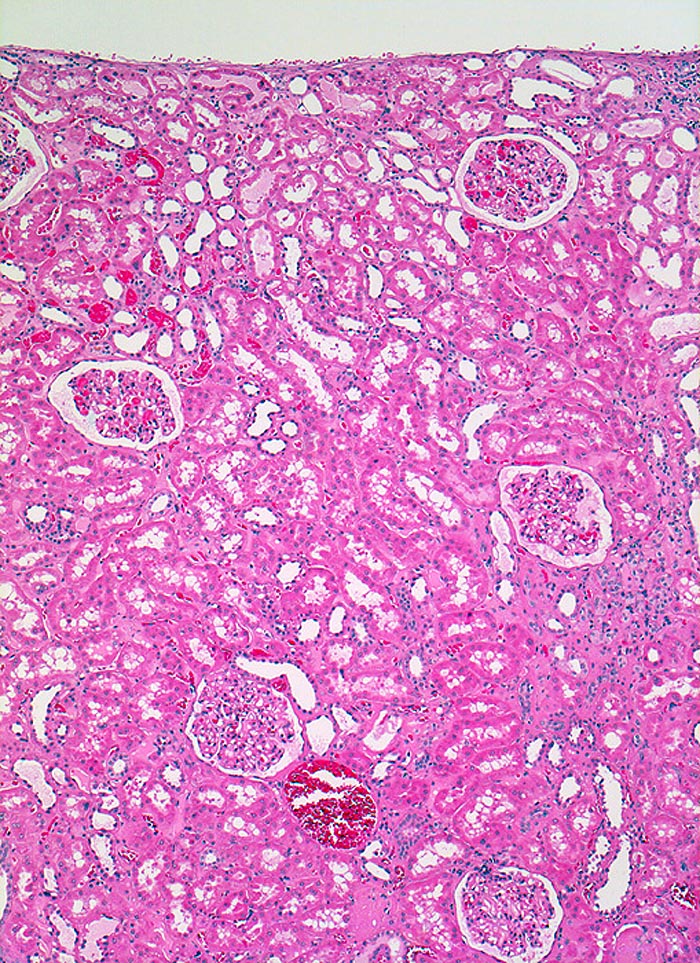

Im allgemeinen ist die Niere infolge von Glomerulumhypertrophie und Tubulushyperplasie vergrössert und derb, die Oberfläche ist granuliert. Bei schwerer Atherosklerose und fortgeschrittener Niereninsuffizienz kann die Niere auch normal gross oder verkleinert sein. Die Kombination von nodulärer Glomerulosklerose, hyalinen Schlingenkappen (=Proteinthromben in den Glomerulumschlingen (> 1916)) oder Kapseltropfen (> 1907) und Arteriolosklerose in Vas afferens und efferens ist beweisend für eine diabetische Nephropathie. Jede einzelne Läsion für sich genommen ist aber unspezifisch. Eine noduläre Glomerulosklerose kann auch vorkommen bei membranoproliferativer Glomerulonephritis (> 2652), Leichtkettenglomerulopathie oder Amyloidose (> 2019). Der nodulären Glomerulosklerose geht bei Diabetikern eine diffuse Glomerulosklerose (> 1906) voraus. Dabei zeigen die glomerulären Basalmembranen und das Mesangium eine progrediente gleichförmige Verbreiterung. Bei der nodulären und diffusen Glomerulosklerose handelt es sich aber wahrscheinlich um zwei pathogenetisch unterschiedliche, sich überlagernde Krankheitsbilder. Typisch bei Diabetikern ist im Unterschied zur arteriellen Hypertonie die Arteriolosklerose von Vas afferens und efferens (> 1911) und oft auch der Vasa recta. Intrarenale Arterien können eine Atherosklerose mit Atheromen zeigen. Subendotheliale Proteinablagerungen teilweise mit Verschluss der Glomerulumschlingen (Schlingenkappen) und knotige Proteinablagerungen in der Bowman'schen Kapselbasalmebran (Kapseltropfen) gehören zu den sogenannten exsudativen Läsionen (> 1919) (> 1920) der diabetischen Nephropathie und führen zu Synechien sowie zur globalen Glomerulosklerose. Gleichzeitig mit den Glomerulumveränderungen treten tubuläre Basalmembranverbreiterungen auf, später eine Tubulusatrophie und interstitielle Fibrose mit Begleitentzündung. Auch die Basalmembranen der peritubulären Kapillaren sind verdickt.

• Verbreiterung der tubulären Basalmembran.

• Tubulusatrophie mit interstitieller Fibrose und Begleitentzündung.